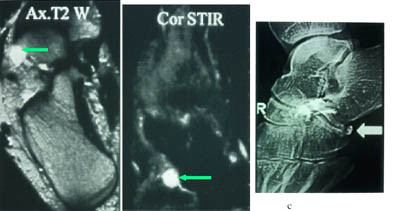

Mesteparten av sinus tarsi er fylt med fett. Dette gir høysignal på T1-vektet sekvensog lavsignal på fettsuppresjonssekvenser. Blodkar og nervefibrer gir små punktformige lavsignaler medialt i fettvevet på T1-vektet sekvens. Ligamentene gir lavsignal på spinnekkosekvensene. Figur 1 viser en normal sinus tarsi. I koronalplanet sees ligamentum cervicale ventralt og ligamentum interosseus noe lenger dorsalt. Det mest fremtredende og hyppigste MR-funnet ved sinus tarsi-syndrom er lavsignalområder på T1-vektet sekvens og lav- eller høysignalområder på T2-vektet sekvens. Forandringene er forårsaket av fibrose (fig 2) med eller uten inflammasjon (fig 3). Av og til kan vi se små væskelokulamenter som representerer ganglioncyster (fig 4). Ligamentene kan være vanskelig å se, enten fordi det er mye inflammasjon eller fordi de er røket. Hos en del pasienter kan man finne ruptur av laterale ankelligamenter, spesielt ligamentum talofibulare anterior.